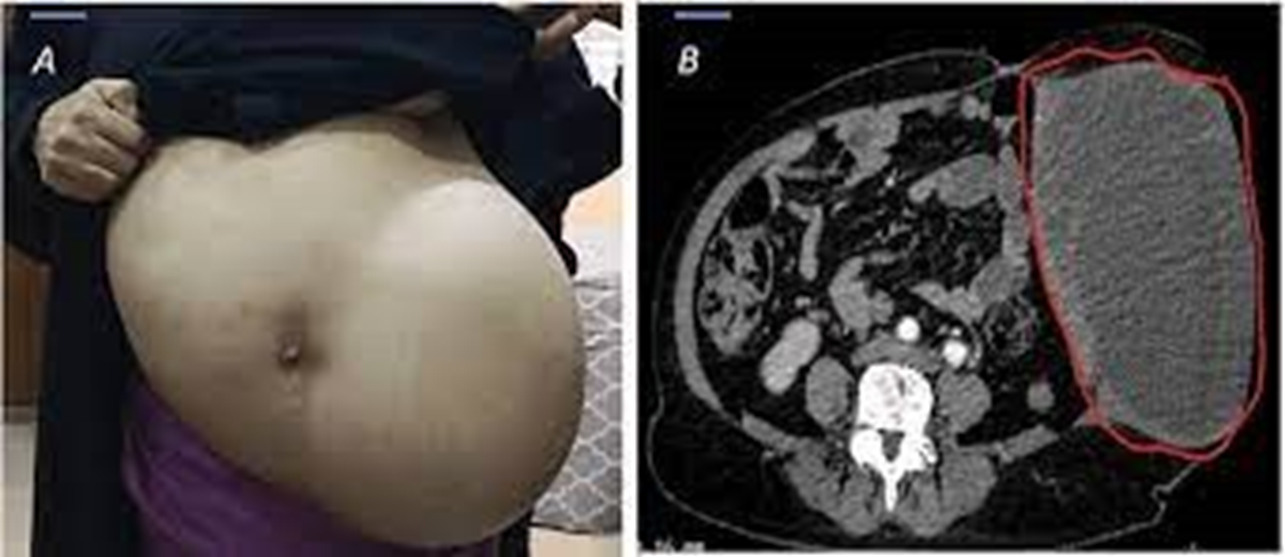

An abdominal mass is one of the most common symptoms of Wilms’ tumor. Parents or healthcare providers may feel a lump or swelling in the child’s abdomen.